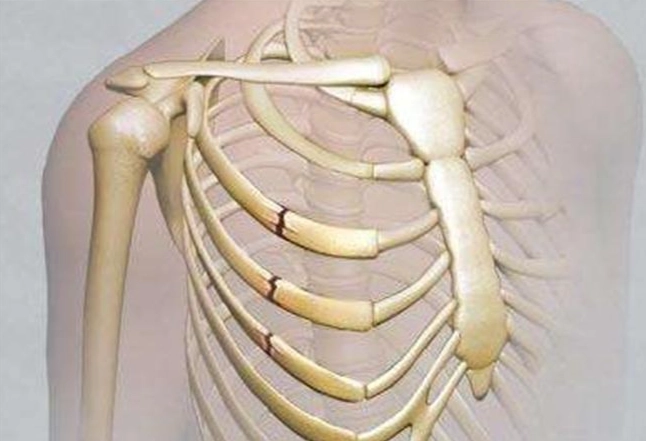

肋骨骨折後,身體會啟動自然的愈合過程,包括炎症期、修復期和重塑期。這段期間,營養攝取直接影響骨骼的再生能力。如果吃了不該吃的東西,可能會干擾這些階段,導致恢復延遲或併發症。例如,高鹽分食物會引起水腫,增加胸腔壓力,讓呼吸都變得更痛苦。而辛辣食物則可能刺激神經,加劇疼痛感。

我記得醫生告訴我,骨折愈合需要大量的蛋白質、鈣質和維生素D。這些營養素能促進骨痂形成,讓斷裂的肋骨慢慢接合。反之,如果攝取過多禁忌食物,就像在傷口上撒鹽,不僅無助恢復,還可能讓情況惡化。所以,肋骨骨折不能吃什麼,絕對不是小事,它關係到整個恢復期的舒適度和效率。

有些研究指出,飲食控制能減少併發症風險,比如肺炎或感染。肋骨骨折常伴隨呼吸困難,如果飲食不當導致腹脹或炎症,可能會讓呼吸更吃力。這點我深有體會,當初因為貪吃鹹酥雞,結果水腫搞得我連深呼吸都痛,真是自作自受。